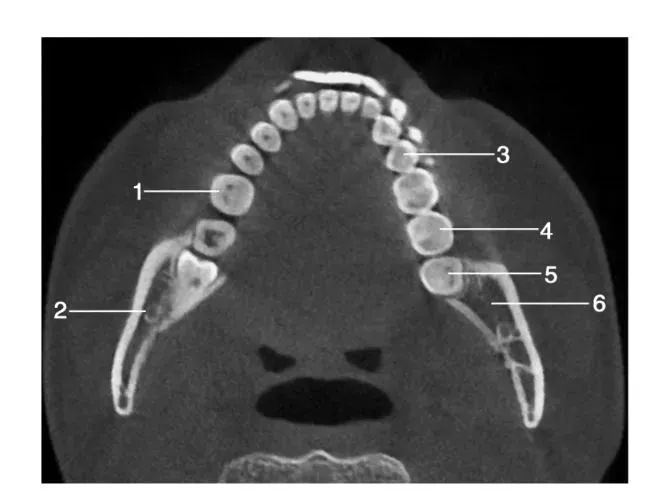

经下颌后牙牙冠处层面水平位图像

1.左下第一磨牙; 2.下颌神经管; 3.左下第二前磨牙 ; 4.左下第二磨牙; 5.左下第三磨牙 ; 6.下颌升支